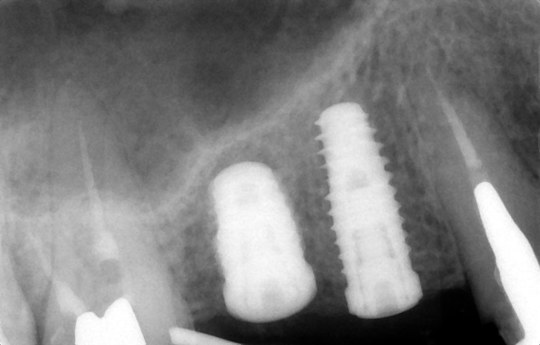

④インプラント埋入後

このようにインプラント予定部位に骨がなくても骨を作る(骨造成)ことができます

治療前

骨造成して完成